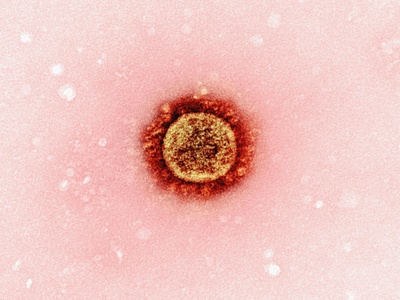

COVID-19

COVID-19 is caused by SARS-CoV-2, commonly producing fever, cough, fatigue and loss of smell; severe cases cause pneumonia and long-term symptoms. Global since 2019; spreads by respiratory routes. Vaccines and masks reduce risk; treatments and antivirals available for high-risk patients.